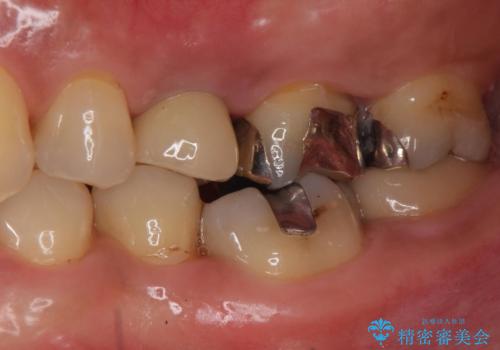

歯茎が腫れる インプラントでの治療

- 40代女性

- 10ヶ月

- 5-10回

- 左上5/インプラント:242,000円 骨増生:55,000円 カスタムアバットメント:110,000円 インプラント用仮歯:22,000円 ジルコニアクラウン:121,000円 合計550,000円費用は治療当時の料金となります